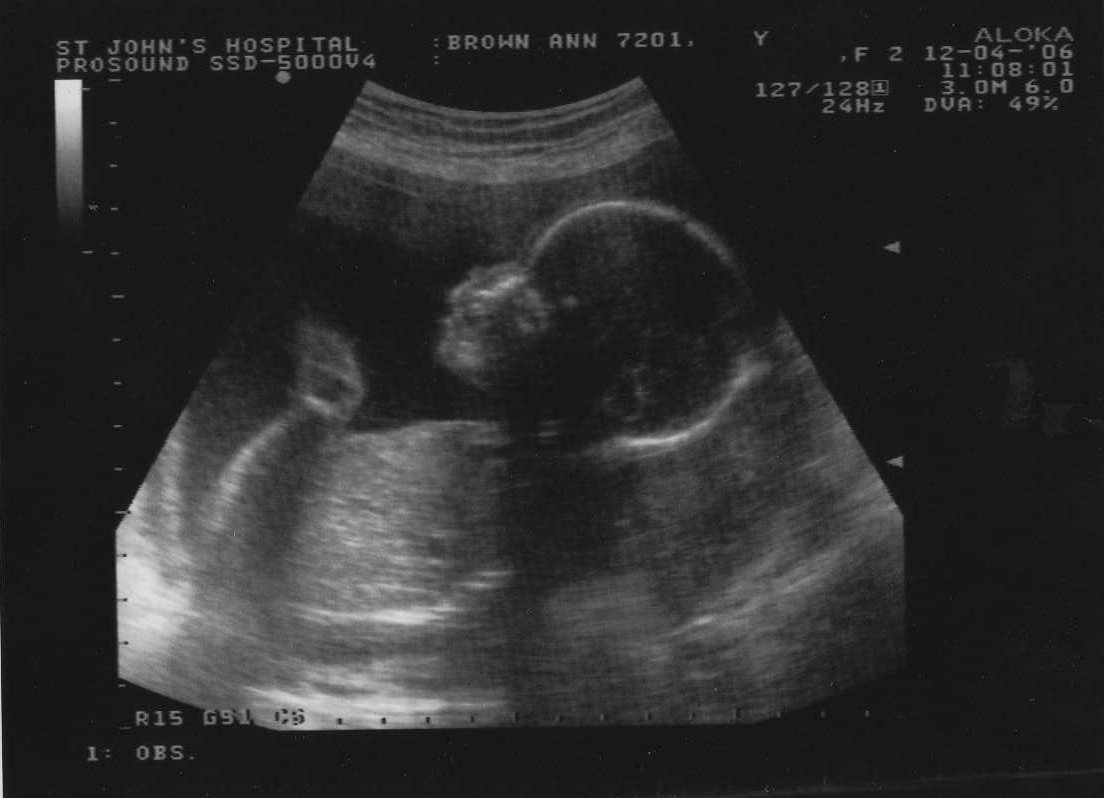

12th April 2006 (20 weeks) ... an ante natal yawn